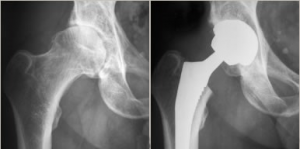

L’arthrose (ou coxarthrose) est l’usure du cartilage de votre hanche. Le cartilage est le revêtement protecteur qui permet aux os de glisser parfaitement l’un sur l’autre, comme un coussinet.

Avec le temps, ce cartilage s’abîme, s’affine et finit par disparaître. Les os se retrouvent alors en contact direct « os contre os ». Ce frottement crée de l’inflammation et devient très douloureux.

Remplacer l'articulation douloureuse.